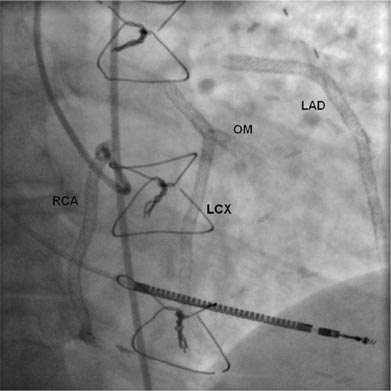

1. Правая коронарная артерия: 1,2,3 сегменты, стеноз с переходом в окклюзию (хроническую, о чем говорят мощная сеть коллатералей и старый инфаркт в анамнезе). Окклюзия с тупым концом (blunt stump), окружена коллатералями (bridging). За хронической окклюзией сегмент визуализируется, но в месте окклюзии отходит одна ветвь больше 1,5 мм, кроме того есть мелкие ветви 0,1,0 по Медина, есть извитость.